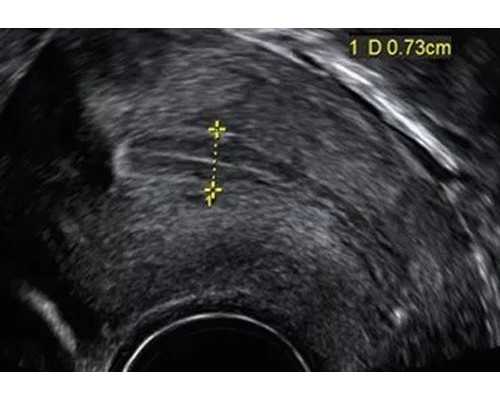

在试管婴儿的旅程中,我们常常会记录下每一个重要的时刻。从最初的期待到最终的喜悦,每一个小小的进步都值得珍藏。即使只是一个0.6厘米的胚胎,也承载着父母满满的爱和希望。通过记录,不仅能增强与胎宝宝的交流互动,更能减轻孕期的焦虑情绪。您可能会发现,怀孕让您变得更加坚韧和有毅力。如果您在考虑代生女孩,这些记录也会为您提供宝贵的参考。